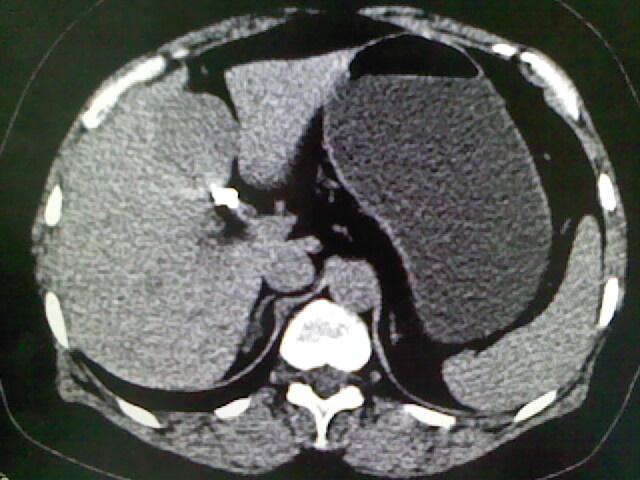

以下是引用卜一在2009-4-2 13:26:00的发言:[br]胆囊颈部结石伴胆囊炎!另:建议增强,待除外肝内占位及胆囊占位!

以下是引用liaoqiang在2009-4-2 16:23:00的发言:[br]胆囊是否切除?胆囊颈区致密影考虑金属夹?结石?肝脏右叶低密度影,考虑增强。